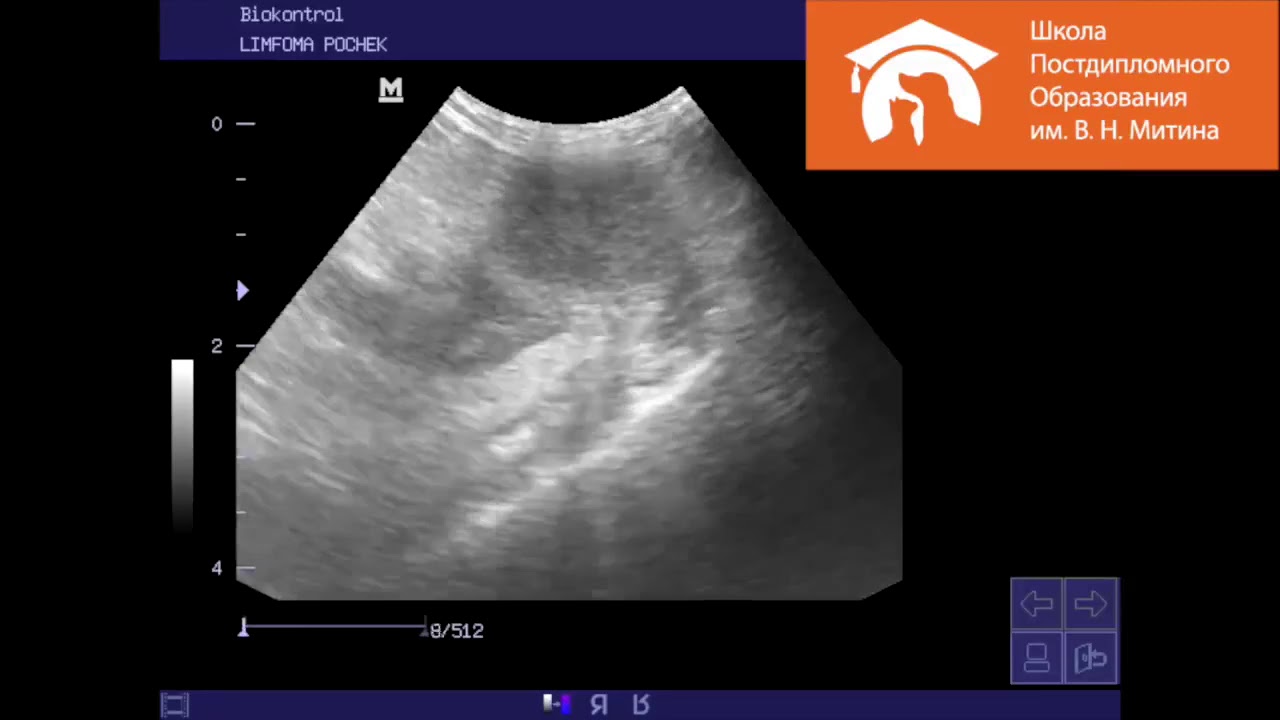

Лимфома у кошек что это 112 фото